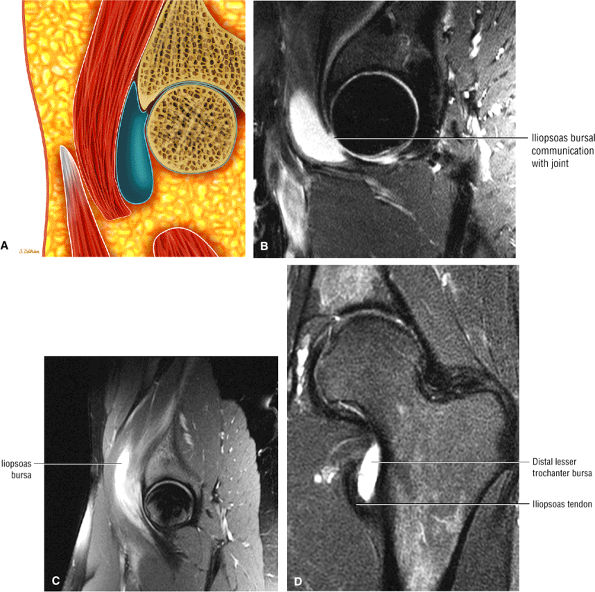

FIGURE 3.29 ● Normal axial anatomy of the hip. (A, B) At this level, the sciatic nerve can be seen exiting the sciatic foramen, deep to the piriformis muscle. Asymmetric enlargement of the piriformis muscle or masses in this region can cause impingement of the sciatic nerve, the so-called piriformis syndrome. (C, D) At this level the transition from the acetabular roof to the top of the femoral head is visualized. The thin arc of dark signal along the lateral margin of the acetabular roof represents the superior margin of the labrum. High signal in the superior labrum can be identified as a labral tear, and accompanying paralabral cysts are commonly identified extending superficial to the labrum. (E, F) The anterior labrum and the posterior labrum on axial images are identified as dark-signal triangles at the lateral margin of the acetabuli. Labral tears present as linear or irregular fluid signal extending through the substance of the labrum, or as expansion of the labrum by fluid signal extending to the surface of the labrum. Fluid signal interposed between the labrum and the acetabulum at the labral attachment indicates labral detachment.(G, H) Tendinosis of the gluteus medius and minimus insertions on the greater trochanter is visualized as thickening and increased signal of the tendons. Trochanteric bursitis can be identified either superficial or deep to the gluteus medius and minimus insertions. (I, J) A fluid collection anteromedial or anterolateral (or both) to the iliopsoas tendon is compatible with iliopsoas bursitis. Occasionally, iliopsoas bursitis may be present adjacent to an anterior labral tear, in which case it may be difficult to distinguish from a paralabral cyst. (K, L) The common hamstring origin on the ischium comprises the biceps femoris and semitendinosus tendons. The common hamstring tendon is a frequent site for tendinosis or partial tears, and the pathology is commonly symmetric.